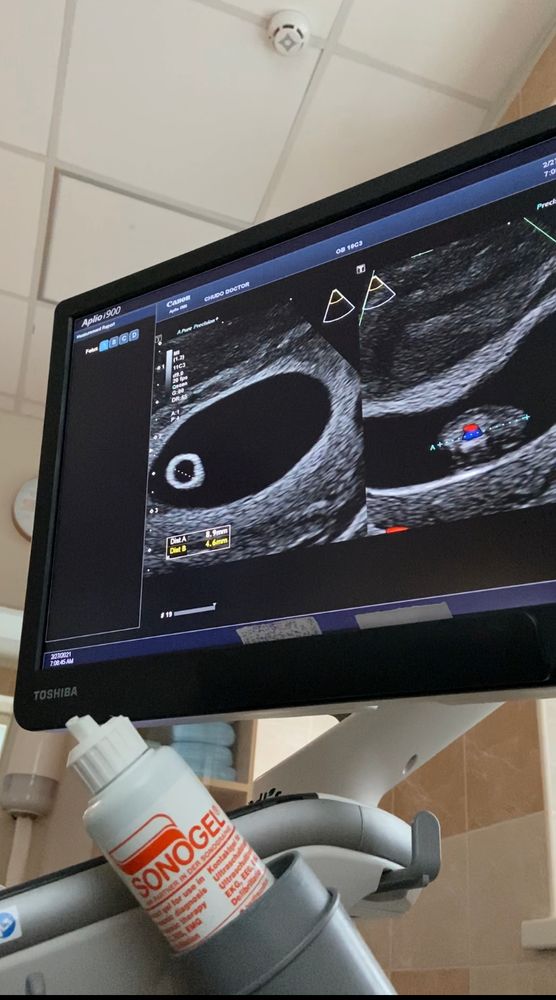

Доброе утро, девочки 💓 Сегодня было контрольное узи, пока трансвагинально, но думаю следующее уже будет через живот.

По месячным срок 6+4

ПЯ 27 мм (8н0д)

КТР 8,9 мм (7н0д)

ЖМ 4,6 мм

Хорион 5 мм

ЧСС 157 уд/мин (я засняла на телефон, чтобы мужу дать послушать, пока он в командировке)